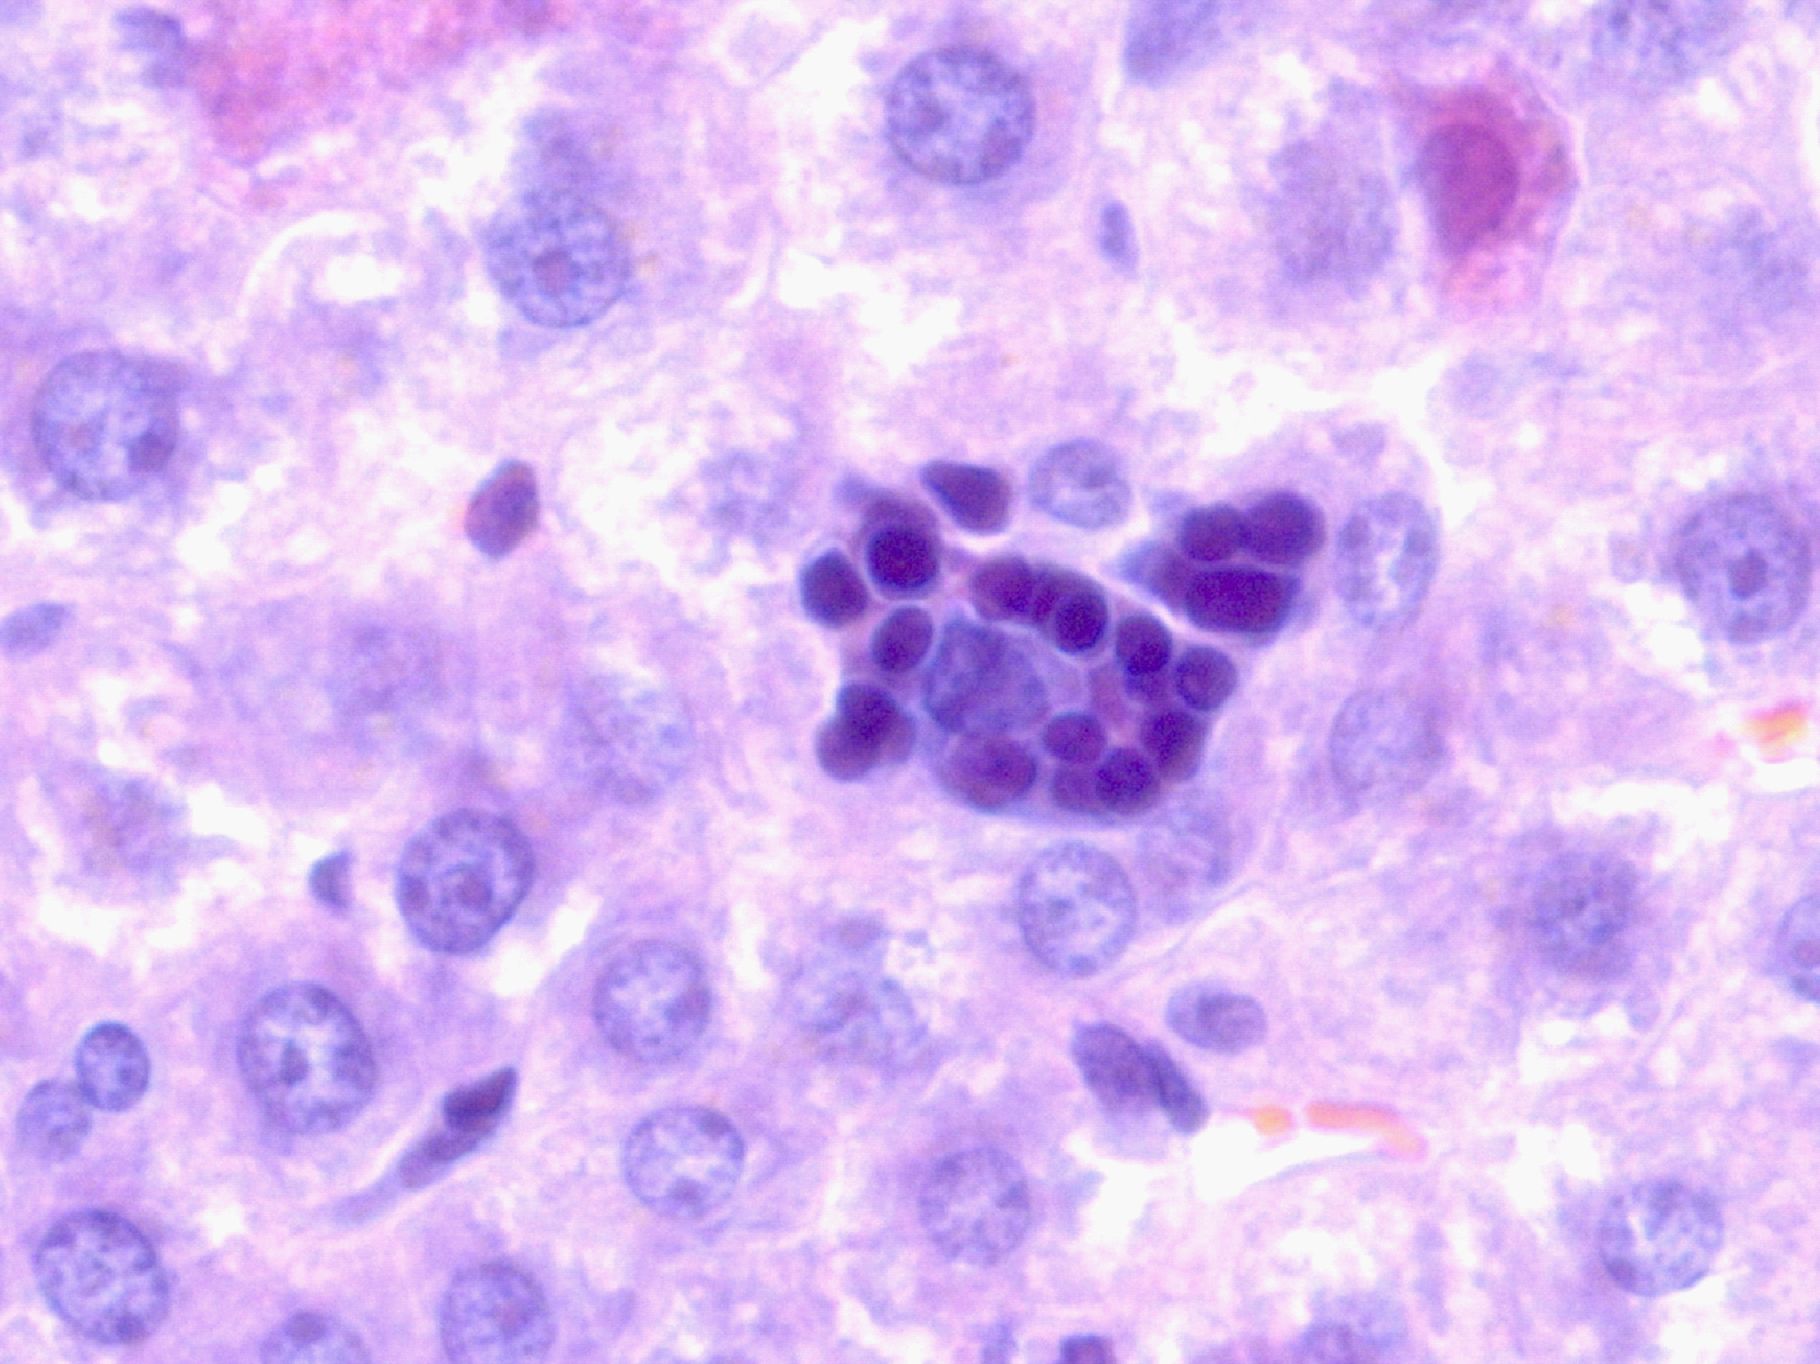

Рисунок 2 – Печень крысы при остром алкогольном гепатите